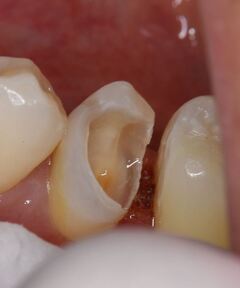

歯は削れば削るほど、もろくなります。歯の表面のエナメル質に無数のひびが入ったり、インレー(歯の詰め物)

(虫歯よりもかなり大きく削る)を装着すると、くさびのような働きをして、歯が割れてしまう事があります。

●大きく削ってインレーを詰めても細菌の取り残しがある→数年後、虫歯の再発

●大きく削ることで、別の痛みが引き起こされる場合がある

●削った部分がむき出しのまま、うがいをさせる。唾液で汚染される→さらなる虫歯や神経の炎症を起こす